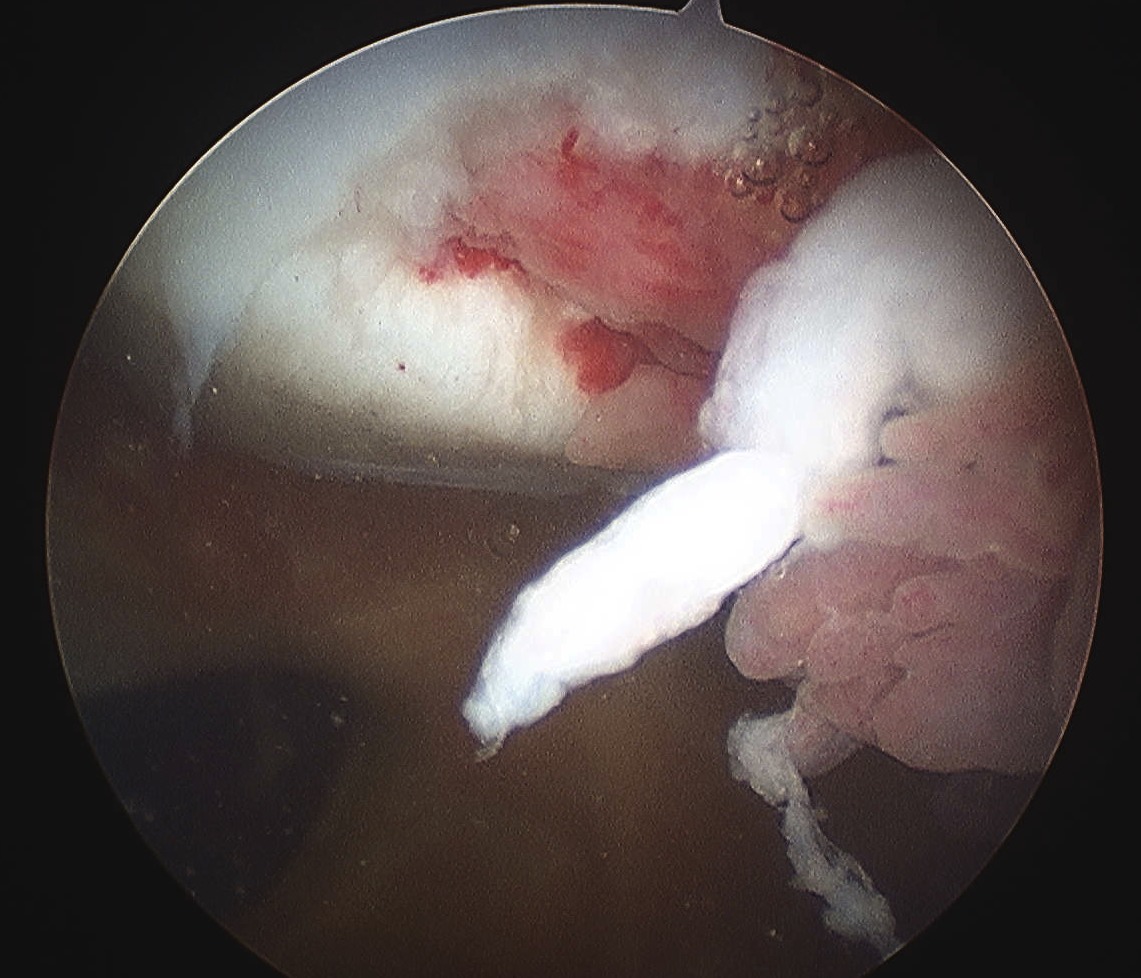

3. Large Chondral piece with minimal or no bone

- can attempt suture fixation

- need to warn of risk of failure and need for reoperation

- careful monitoring

4. Large irreparable chondral lesion

- remove loose body

- microfracture / abrasion initially

- if continue to be asymptomatic, consider alternative procedure

- MACI / mosaicplasty